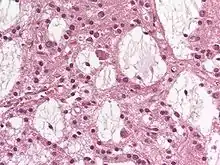

Dysembryoplastic neuroepithelial tumour (DNT, DNET) is a type of brain tumor. Most commonly found in the temporal lobe, DNTs have been classified as benign tumours.[1] These are glioneuronal tumours comprising both glial and neuron cells and often have ties to focal cortical dysplasia.[2]

Dysembryoplastic neuroepithelial tumours are largely glioneuronal tumours, meaning they are composed of both glial cells and neurons.[2]

Three subunits of DNTs have been commonly identified:[2]

- Simple: Specific glioneuronal elements are the sole components of simple DNTs.[2]

- Complex: Glial nodules and/or type 3b focal cortical dysplasia (FCD), in addition to the glioneuronal elements are present in complex DNTs.[4] Both the nodules and FCD can be present within the same tumour, though only 47% of complex DNTs are linked to FCD.[2]

- Nonspecific: Nonspecific DNTs are lacking the glioneuronal elements common to DNTs but will show glial nodules and/or type 3b FCD.[2] Eighty-five percent of nonspecific case of DNTs show this FCD.[2]

There currently exists some debate over where to make the proper division for the subunits of DNTs. A fourth subunit is sometimes noted as a mixed subunit. This mixed subunit expresses the glial nodules and components of ganglioglioma.[1] Other findings suggest that DNTs require a reclassification to associate them with oligodendrogliomas, tumours that arise from solely glial cells.[3] These reports suggest that the neurons found within DNTs are much rarer than previously reported. For the neurons that are seen in the tumours, it is suggested that they had been trapped within the tumor upon formation, and are not a part of the tumour itself.[3]